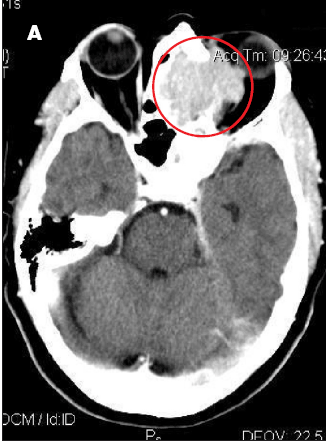

The patient had moderate proptosis; extraocular motions of the left eye were restricted in all directions. She had no lymphadenopathy. Oropharynx was visually unremarkable; however, fiberoptic nasopharyngoscopy revealed a posterior superior nasal cavity mass. A contrast CT scan of the head showed a large mass lesion at the level of the ethmoid sinus, eroding into the left orbit and displacing the left globe (A).

MRI of the head showed a 5.3 x 4.2 x 4.2-cm enhancing mass at the base of the brain that extended into the nasal cavity, with erosion into the cribriform plate, ethmoid sinuses, and planum sphenoidale. Results of an ethmoid sinus mass biopsy confirmed high-grade diffuse large B-cell lymphoma. Staging CT scans showed no metastatic disease, and cerebrospinal fluid analysis revealed no malignant cells. A bone marrow biopsy specimen showed no evidence of light chain monoclonality, no overt evidence of B-cell lymphoproliferative disorder on flow cytometry analysis, and no lymphoma. This was consistent with stage IAE disease.

In this patient, treatment with R-CHOP chemotherapy for 6 cycles resulted in excellent clinical and radiological response (B).